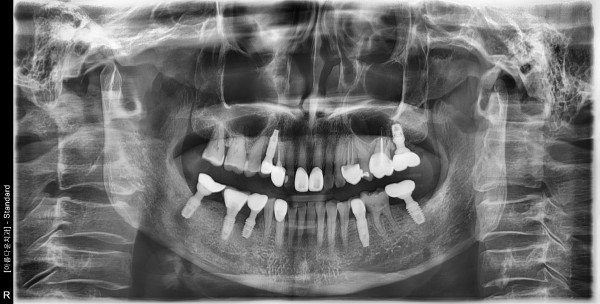

60대 여성 임플란트 식립